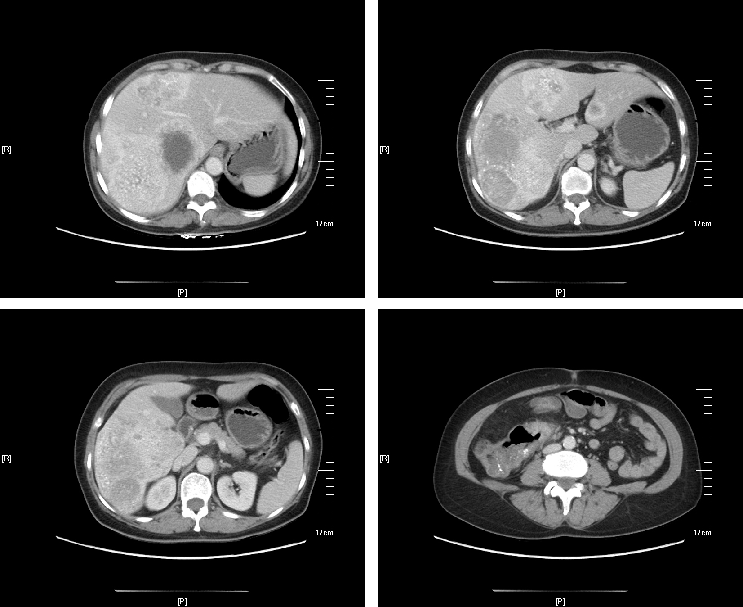

治疗后,原发灶及转移灶明显缩小,肿瘤标志物明显下降。

△治疗前

右肝转移灶明显缩小,左肝转移灶消失,残肝体积足够,意外达到成功转化,分期行原发灶及肝转移根治性切除手术,且原发灶和转移灶术后病理均达到pCR。术后继续完成围手术期化疗,并定期随访,现无瘤生存。